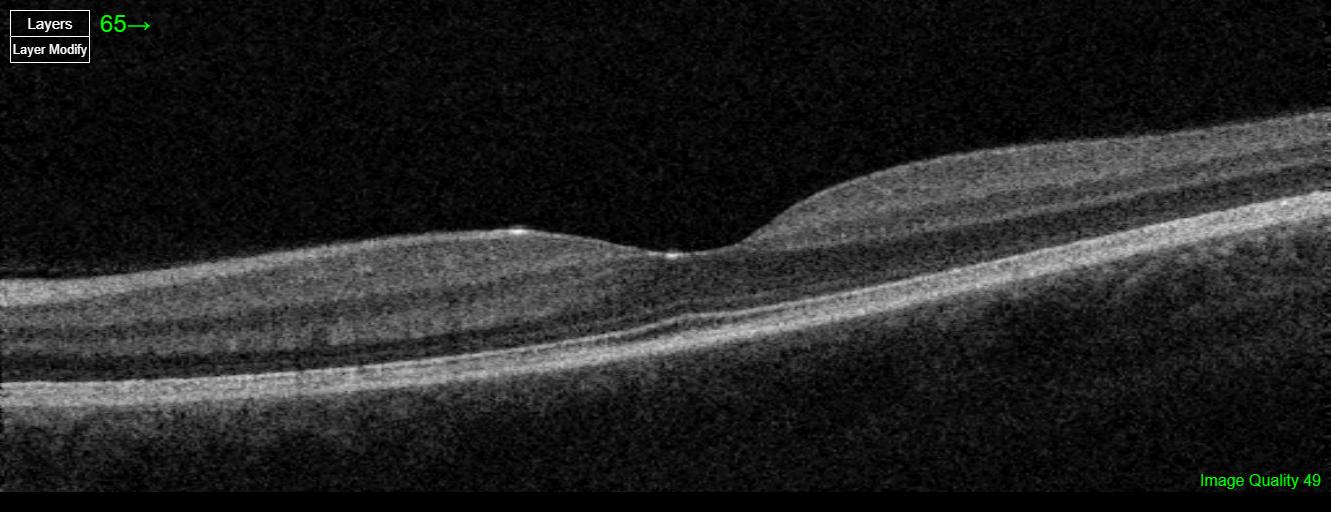

This patient’s symptoms and imaging findings are consistent with trauma-related vitreous disruption. Fundus photos show intraretinal hemorrhages, and OCT reveals slight alteration of the foveal contour. Vitreous disruption after trauma is common and may progress to posterior vitreous detachment. The patient should be advised about warning signs of retinal detachment.

Posterior Vitreous Detachment (PVD) is the separation of the posterior vitreous cortex from the neurosensory retina, typically caused by age-related vitreous liquefaction and weakening of vitreoretinal adhesions. It often begins in the perifoveal region and progresses to involve the optic disc, sometimes producing a Weiss ring. While commonly asymptomatic, vitreous traction at points of strong adhesion can lead to retinal tears or detachment. PVD becomes increasingly prevalent with age and occurs earlier in myopic eyes or following trauma or intraocular surgery.